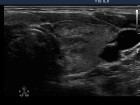

First examination (first row):

Clinical presentation: A 29-year-old woman was referred for evaluation of complaints suggesting hyperthyroidism. She had no eye signs.

Palpation: Both lobes were enlarged. No nodule was palpable.

Ultrasonography: Both lobes were enlarged, moderately hypoechogenic, inhomogeneous and displayed increased vascularization.

Diagnosis: Graves' hyperthyroidism.